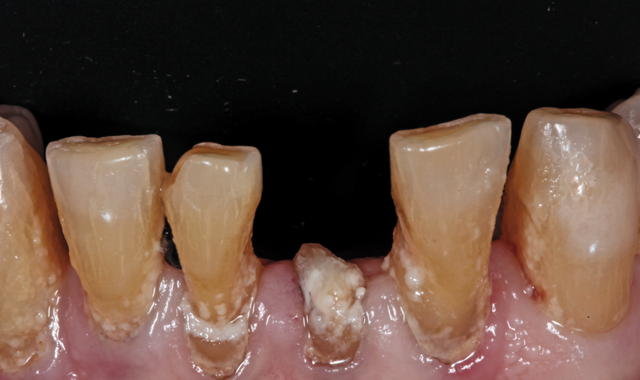

Fig. 2

root surface of the lower incisors-which was visible on the radiograph (Fig. 3)-is known as “Riffle-ization.” Described by Dr. Riffle as a technique for removing every last bit of calculus during repeated root scaling, what is now known as “Riffle-izing," ultimately-over the years-changes the shape of the neck of the tooth to resemble an hour glass.

Therefore, based on the clinical and visual evaluation, the preferred treatment would be to restore the fractured #25 with a post and crown and four splinted crowns to restore the anatomy of the four incisors and increase their resistance to both mobility and fracture.